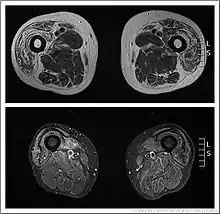

Inclusion body myositis MRI

Muscle imaging can help establish the pattern of muscle involvement and selection of a biopsy site.[3]